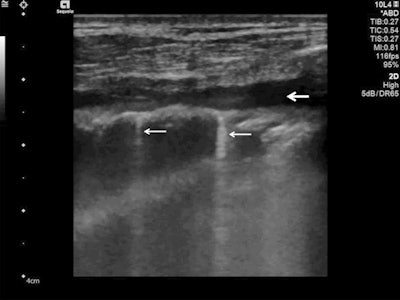

Follow-up of an intensive care unit patient with COVID-19 pneumonia after mechanical ventilation. An indirect sign of recovery is the appearance of A-lines (white arrows) through the recovery phase. No major pleural fragmentation (bold white arrow) is seen, but a mirror effect is visible (left white arrow). All figures courtesy of Dr. Dirk-André Clevert and colleagues and Insights into Imaging.Lung ultrasound in experienced hands can give results that are comparable to chest CT and even superior to standard chest radiography for assessment of pneumonia and/or adult respiratory distress syndrome (ARDS), they explained.

A-lines are reverberation artifacts triggered by oscillating tissue with an air interface, causing the ultrasound waves to be reflected strongly and to reverberate. Among the probe and lung surface, the ultrasound waves bounce back and forth. A-lines are parallel horizontal repetition lines of the pleural surface, appearing deeper on the display screen.

Ultrasound detected A-lines using an abdominal probe. A-lines (white arrows) appear as bright horizontal lines deep to the pleural line (bold white arrow).Due to the fact that this is a classic reverberation artefact, the distance from the skin to the pleural surface equals the distance from the pleural line to the first A-line, the first A-line to the second A-line, etc. The A-profile is shaped by intact ("dry") lung parenchyma containing air when it is combined with normal lung sliding. If sliding is absent, it is intensely suggestive of a pneumothorax.